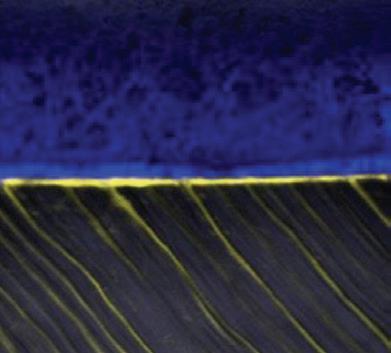

STELA GAP-FREE BONDING INTERFACE

A confocal micrograph of a gap-free Stela-dentine interface. Note the penetration depth of Stela Primer (yellow) within the dentine tubules.

20 µm

Source: Dr Salvatore Sauro